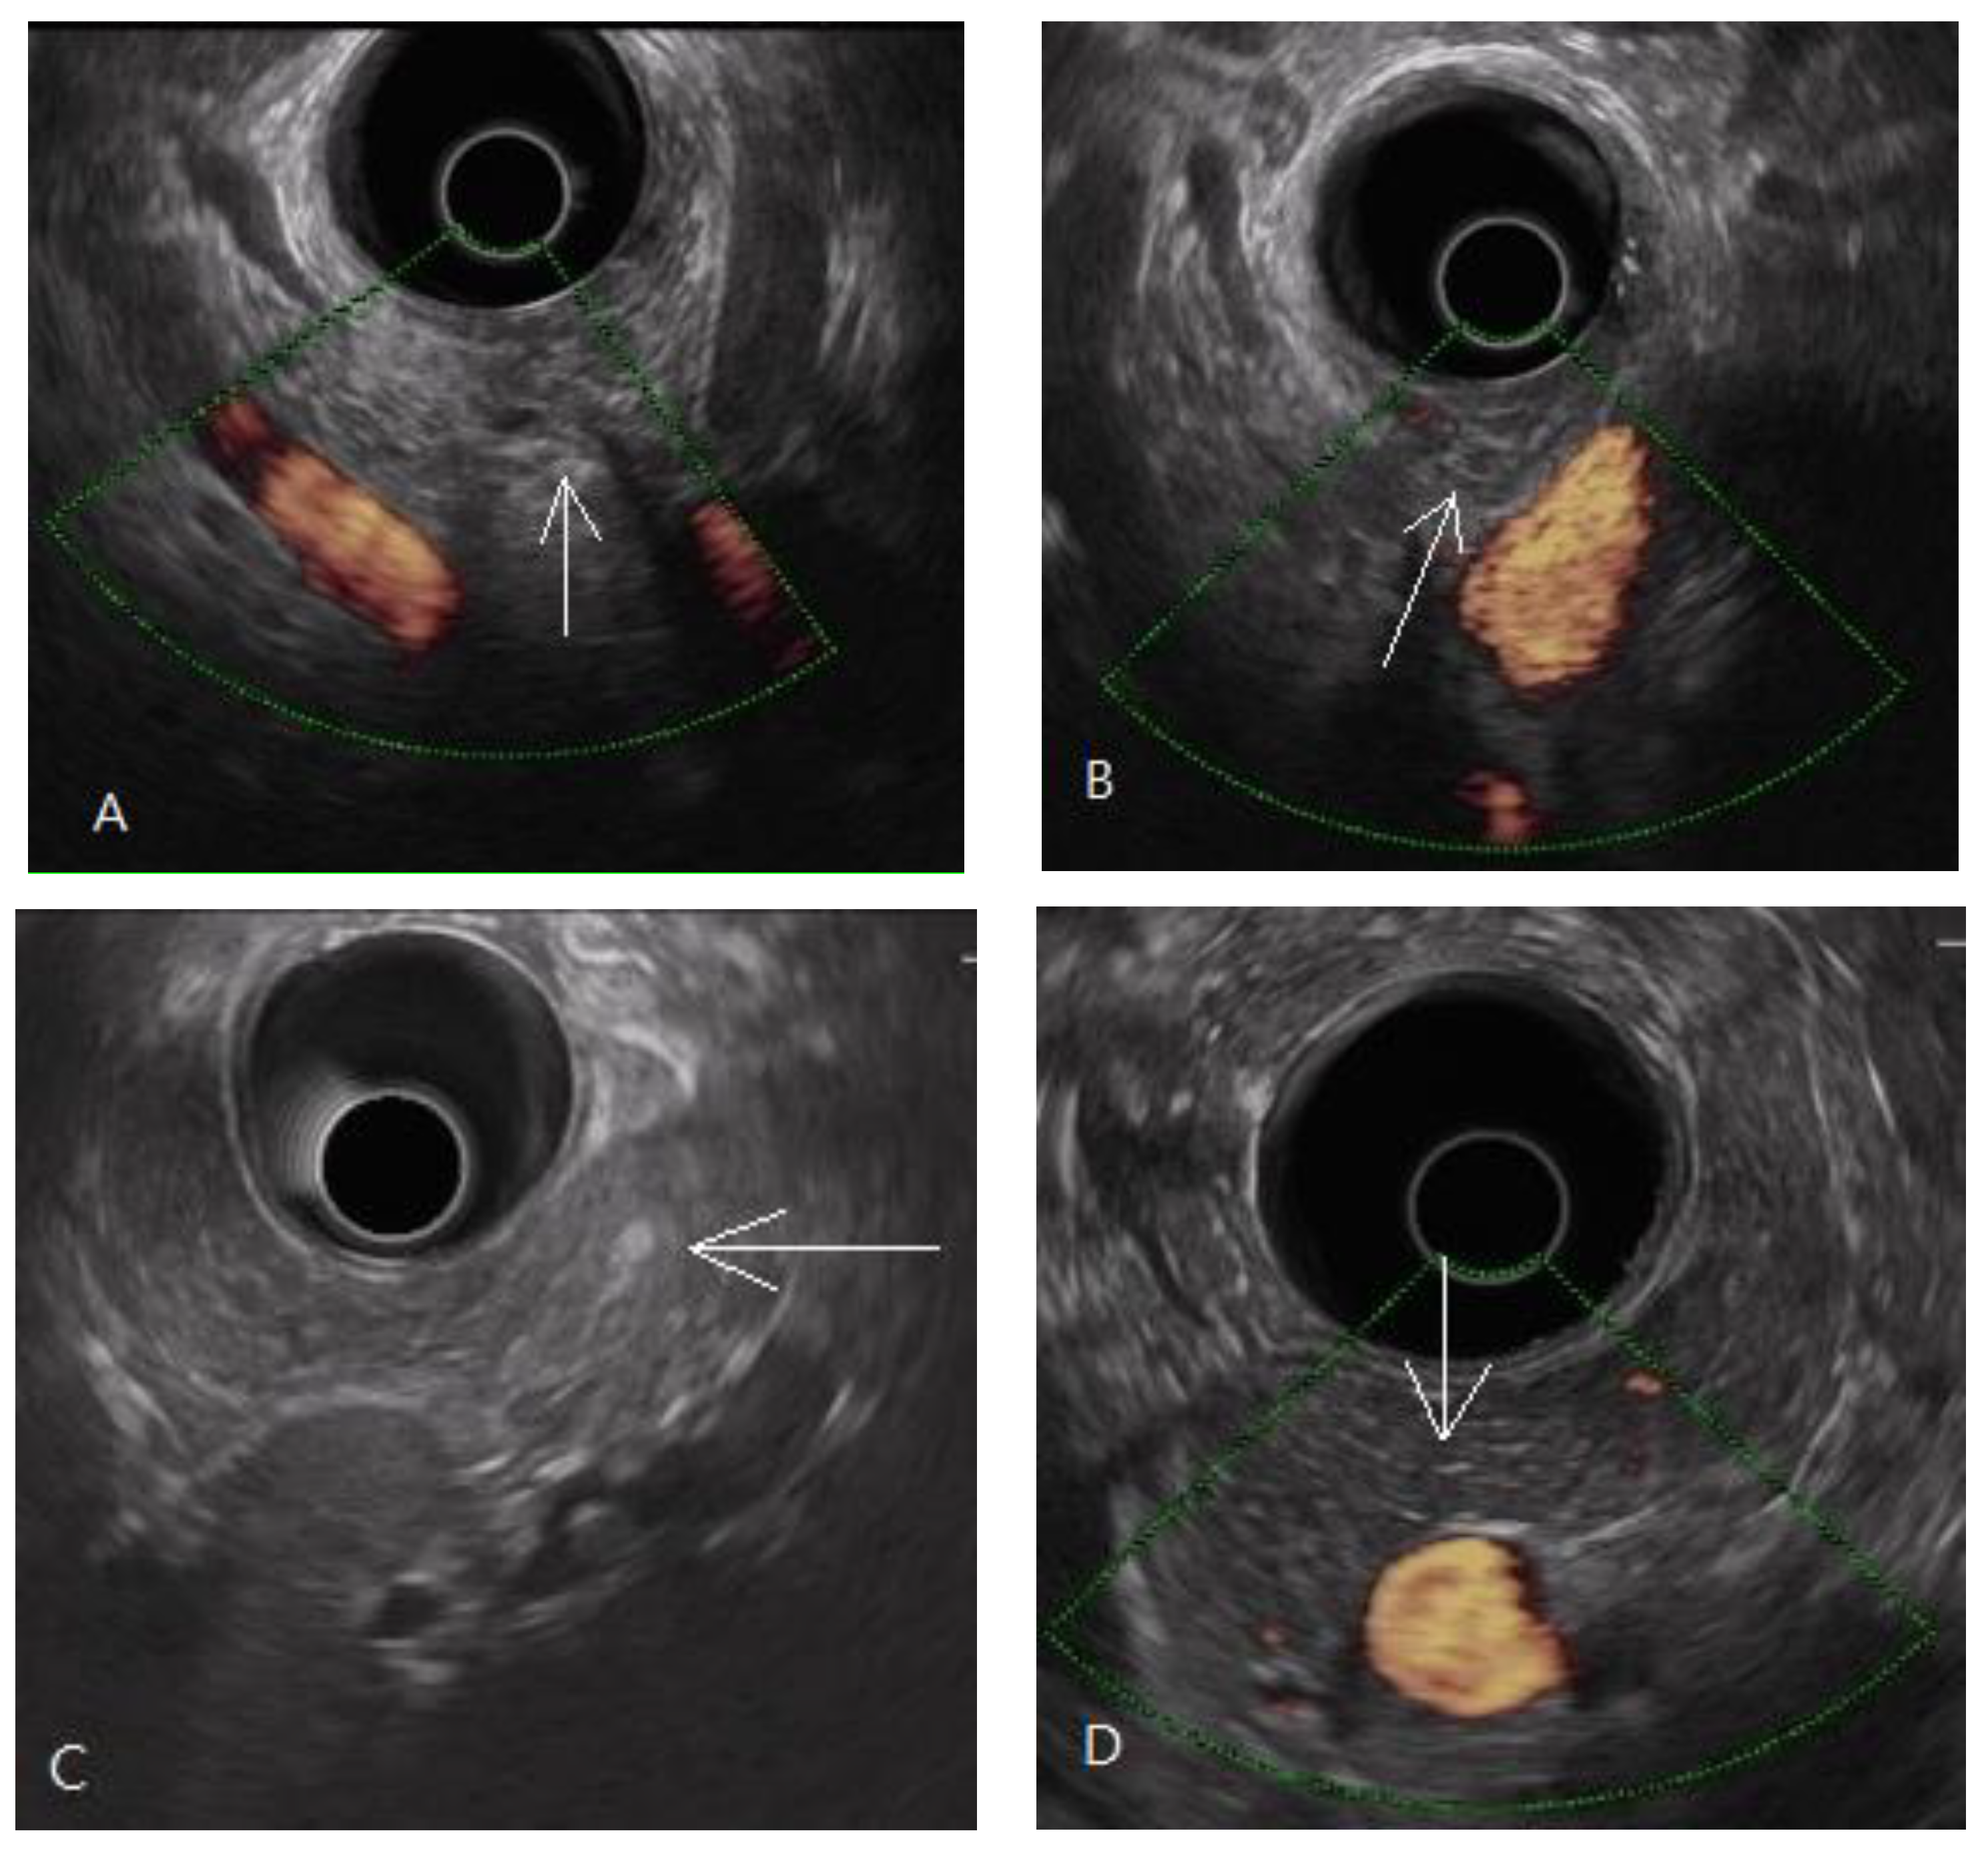

- Yamashita, Y.; Tanioka, K.; Kawaji, Y.; Tamura, T.; Nuta, J.; Hatamaru, K.; Itonaga, M.; Yoshida, T.; Ida, Y.; Maekita, T.; et al. Utility of Elastography with Endoscopic Ultrasonography Shear-Wave Measurement for Diagnosing Chronic Pancreatitis. Gut Liver 2020, 14, 659–664. [Google Scholar] [CrossRef]

- Yamashita, Y.; Tanioka, K.; Kawaji, Y.; Tamura, T.; Nuta, J.; Hatamaru, K.; Itonaga, M.; Ida, Y.; Maekita, T.; Iguchi, M.; et al. Endoscopic ultrasonography shear wave as a predictive factor of endocrine/exocrine dysfunction in chronic pancreatitis. J. Gastroenterol. Hepatol. 2021, 36, 391–396. [Google Scholar] [CrossRef] [PubMed]